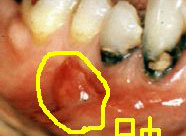

深齲蛀牙

牙髓發炎

根尖周炎

牙髓壞死

殘冠殘根